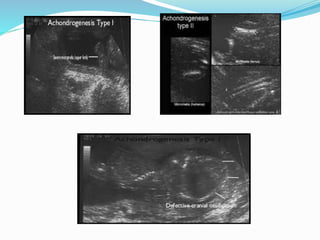

Achondrogenesis

 KEY Finding :

 1- Severe micromelia (shortened bones)

 2- Hypomineralization (bone unusally anechoic)

 3- Fetal hydrops + hydramnios (late)

Types

 Hint : All involve extremely short long bone and

severity is according to involvement of calvarium and

vertebral column.

 Type 1: Calvarium and Vertebral column severly

hypomineralized.

 Type 2 : Calvarium is ossified but veterbral column

may or may not be ossified

 Type 3: Mildest form where hypomineralization only

includes cervical and caudal vertebrae

Prognosis

 All 3 types are lethal at or before birth

 Recurrence is 1:4 in type1 and is a new Dominant

mutation in types 2 and 3 .

Achondrogenesis  KEY Finding:  1- Severe micromelia (shortened bones)  2- Hypomineralization (bone unusally anechoic)  3- Fetal hydrops + hydramnios (late)

Types  Hint :All involve extremely short long bone and severity is according to involvement of calvarium and vertebral column.  Type 1: Calvarium and Vertebral column severly hypomineralized.  Type 2 : Calvarium is ossified but veterbral column may or may not be ossified  Type 3: Mildest form where hypomineralization only includes cervical and caudal vertebrae

Prognosis  All 3types are lethal at or before birth  Recurrence is 1:4 in type1 and is a new Dominant mutation in types 2 and 3 .